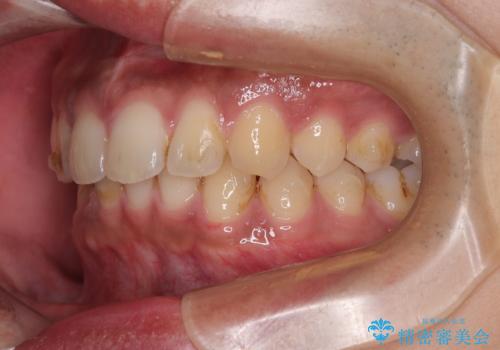

- 上の前歯の正中離開(すきっ歯)と、下顎前歯部の叢生(デコボコ)を主訴に来院された患者様の症例です。

「目立ちにくい装置で治療したい」とのご希望があり、透明のマウスピース矯正であるインビザラインを用いて矯正治療を行いました。

正中離開は舌の癖(舌突出癖)がある場合、後戻りしやすい傾向があります。

そのため当院では矯正治療と並行して、正しい舌の位置・飲み込み方・呼吸の仕方などをトレーニングする

**MFT(口腔筋機能療法)**を実施し、治療後の安定性を高めています。